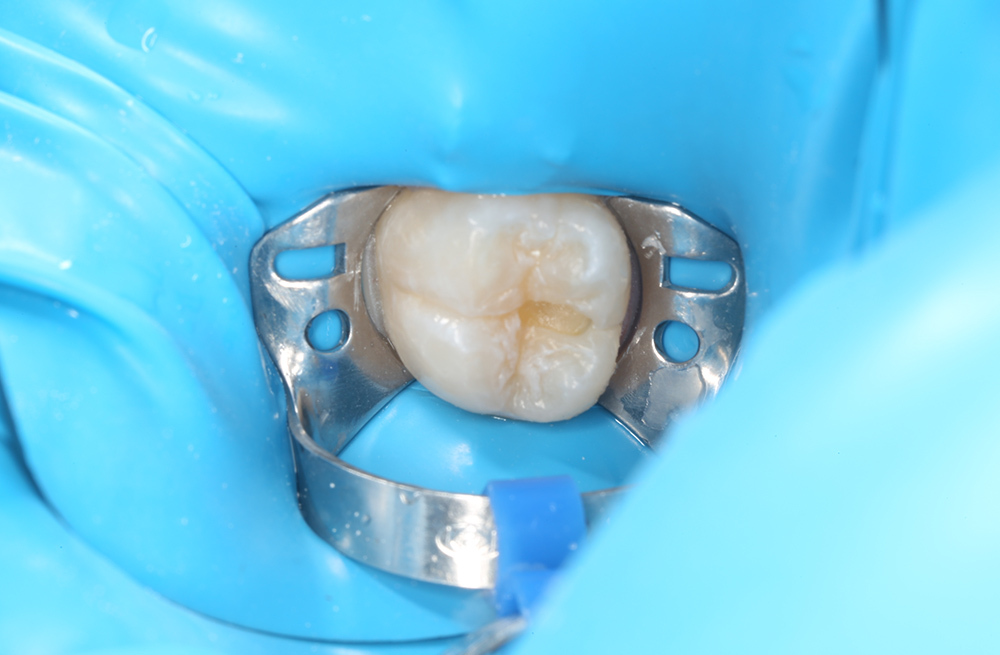

Лечение кариеса на жевательной поверхности постоянного зуба у подростка